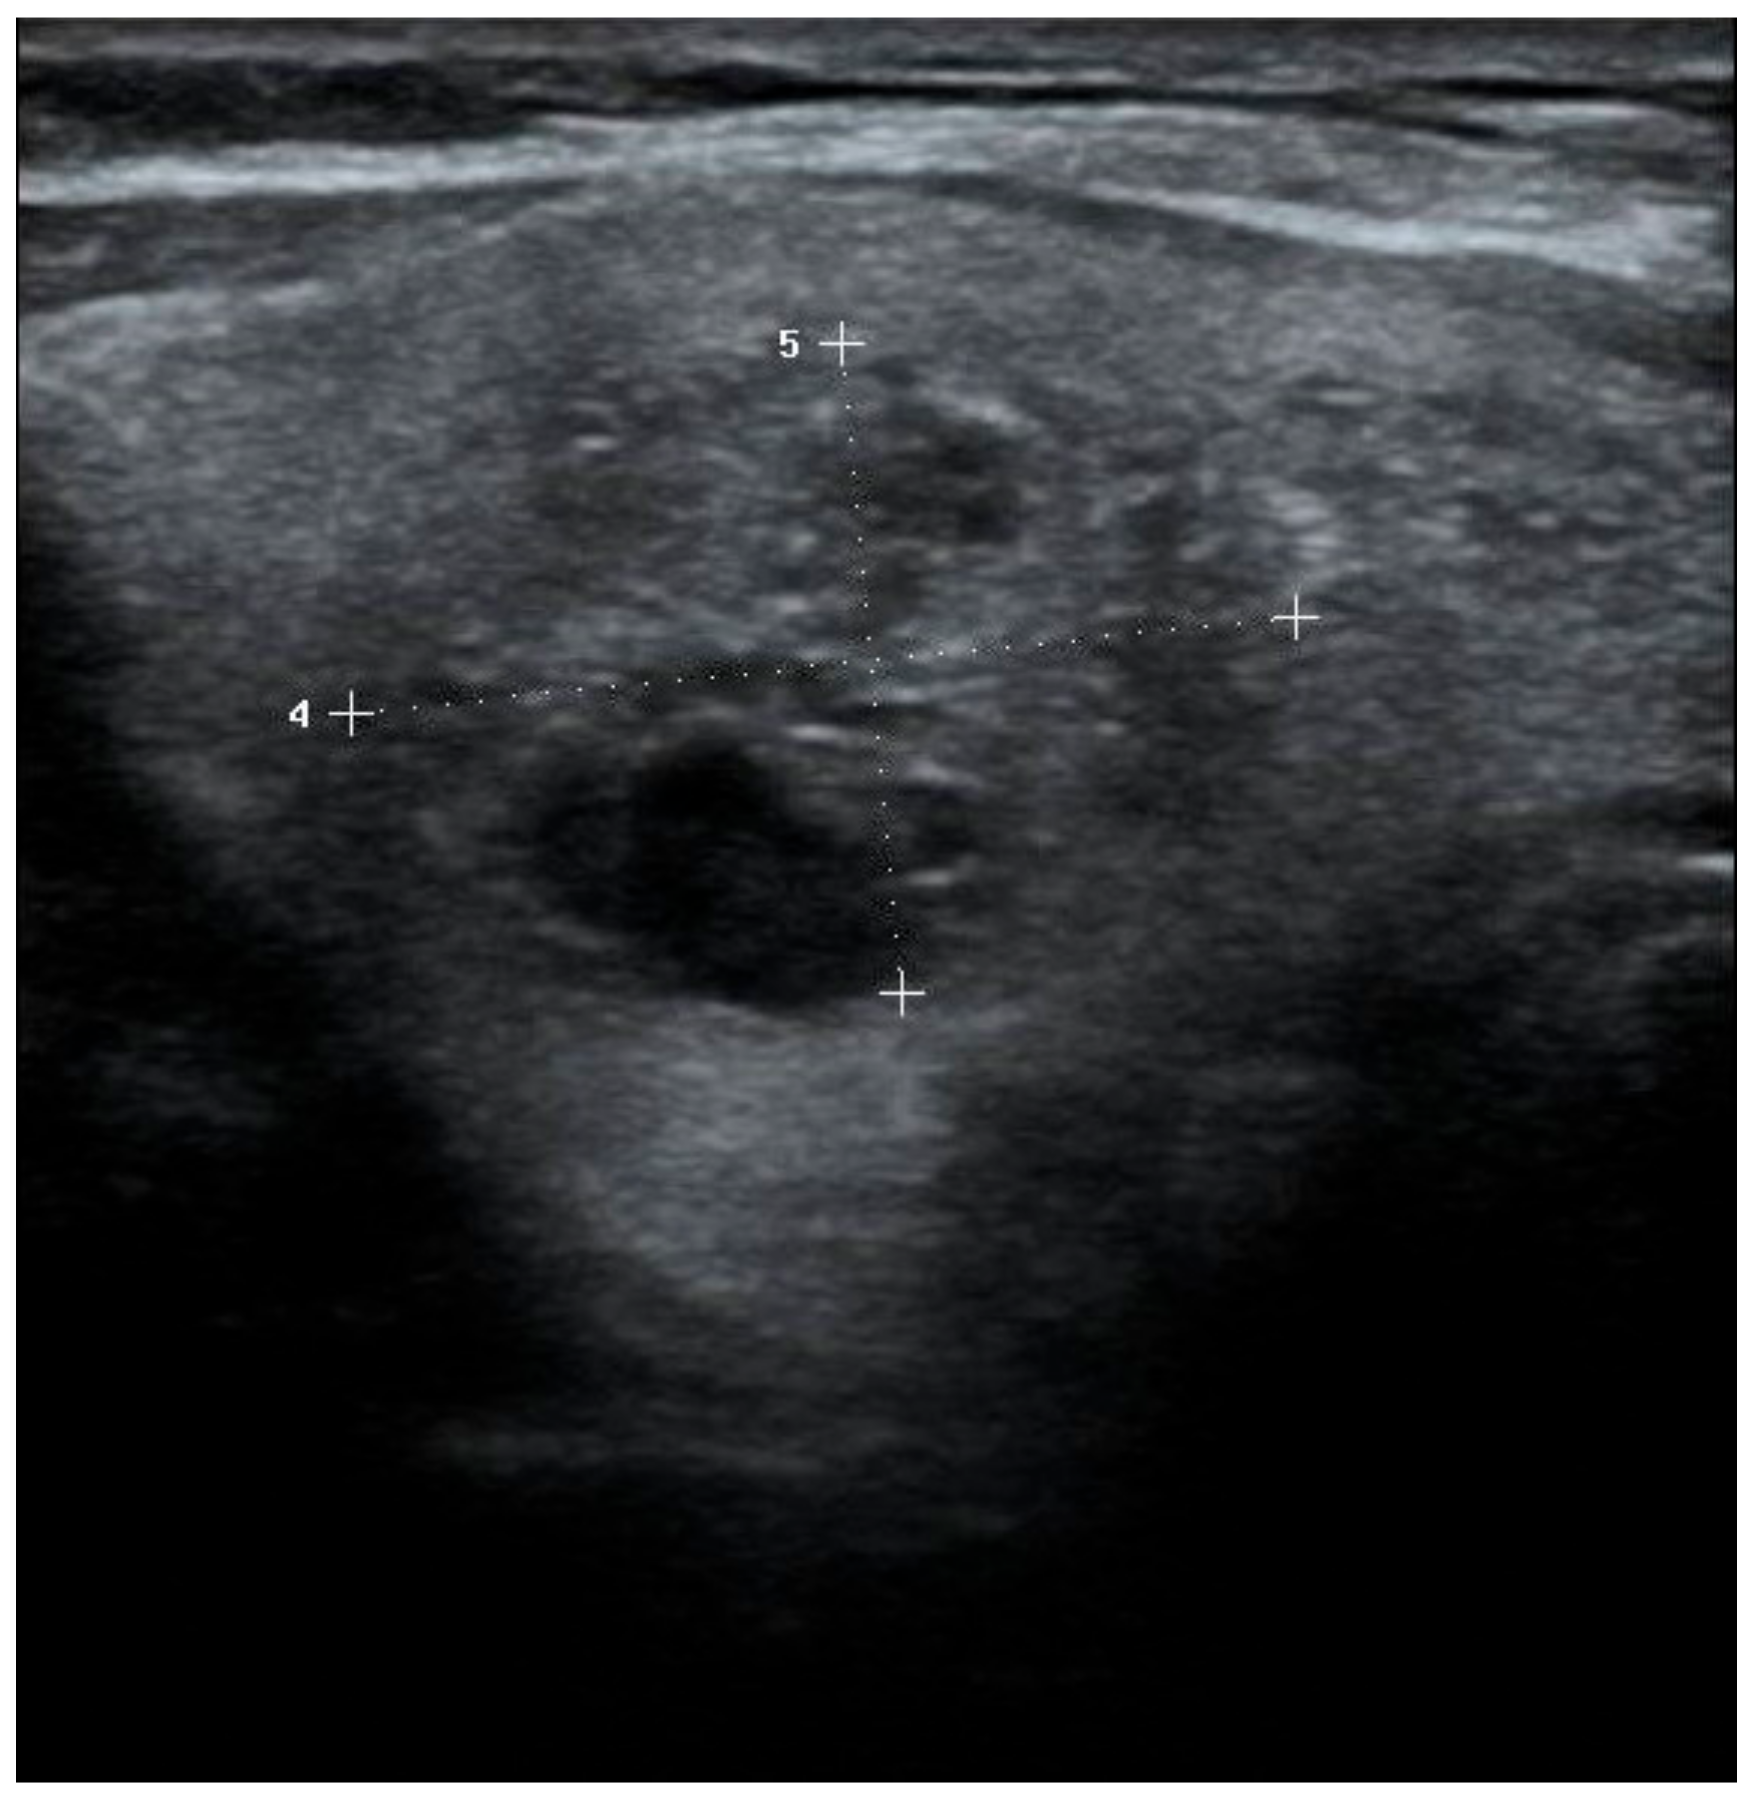

| Size | Composition | Echogenicity | Shape | Margin | Echogenic Foci | TIRADS System | |||

|---|---|---|---|---|---|---|---|---|---|

| ACR | EU | K | |||||||

| 1 | 13 mm | Solid | Hyperechoic | W > T | Smooth | Microcal. | 4 q | 5 | 4 |

| 2 | 12 mm | Solid | Hyperechoic | W > T | Smooth | Microcal. | 4 q | 5 | 4 |

| 3 | 13 mm | Solid | Hypoechoic | W > T | Smooth | None | 4 q | 4 q | 4 |

| 4 | 14 mm | Solid | Hyperechoic | T > W | Smooth | None | 4 q | 5 | 4 |

| 5 | 24 mm | Solid | Hyperechoic | W > T | Smooth | None | 3 q | 3 | 3 |

| 6 | 14 mm | Solid | Hyperechoic | W > T | Smooth | Microcal. | 4 q | 5 | 4 |

| 7 | 17 mm | Solid | Hyperechoic | W > T | Smooth | Rim | 4 | 3 q | 3 q |

| 8 | 12 mm | Solid | Hypoechoic | W > T | Smooth | None | 4 q | 4 q | 4 |

| 9 | 15 mm | Solid | Hyperechoic | W > T | Smooth | None | 3 q | 3 q | 3 q |

| 10 | 18 mm | Solid | Hyperechoic | W > T | Smooth | None | 3 q | 3 q | 3 q |

| 11 | 14 mm | Solid | Hypoechoic | W > T | Irregular | None | 4 q | 5 | 5 |

| 12 | 12 mm | Solid | Hyperechoic | W > T | Smooth | Microcal. | 4 q | 5 | 4 |